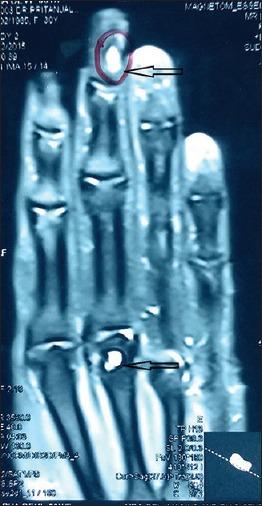

Glomus Tumour with Intramedullary Bone Cyst: A Rare Presentation.

J Cutan Aesthet Surg. 2017 Apr-Jun;10(2):114-116. doi: 10.4103/JCAS.JCAS_54_15.

Glomus Tumour with Intramedullary Bone Cyst: A Rare Presentation.伴有髓内骨囊肿的血管球瘤:一种罕见的表现。